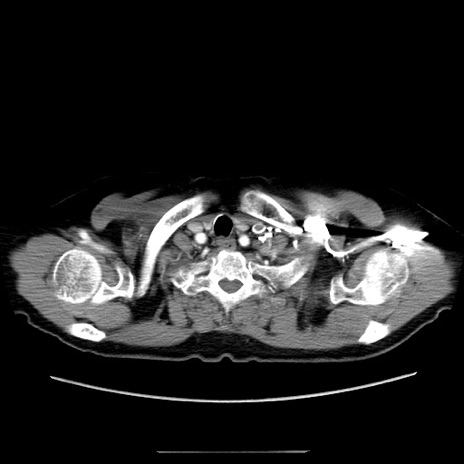

症例5(横断像)

【症例】70歳代女性

【主訴】お腹が張る

【現病歴】1週間くらい前から腹部膨満の自覚あり。昨日夜から増悪したため、本日救急外来受診。

【身体所見】意識清明、BT 36.5℃、BP 165/106mmHg、HR 80bpm、SpO2 98%、腹部:膨満、軟、自発痛・圧痛なし、触診にて不快感あり、腸蠕動音:減弱

【データ】WBC 12600、CRP 1.04